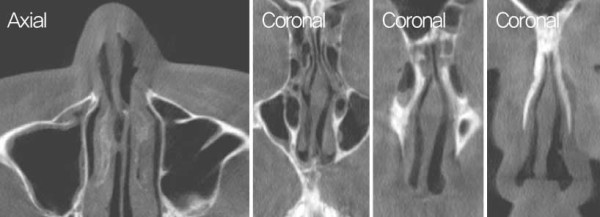

수술장 소견상 cleft nose로 인해 nasal spine이 우측 으로 전위되어 있으며, 비중격 상단부는 좌측으로 만곡 되어 있고, 미단부는 우측으로 전위된 양상이었다. 또 한, 비익연골은 우측이 좁고 좌측은 낮고 퍼져 있었다. BC junction에서 nasal spine까지 비중격연골을 spreader graft를 시행하여 좌측 상단부의

만곡을 교정하였다.

![]()

비중격 및 비밸브 교정 후. 비중격을 nasal spine 좌측으로 이동시키고, bone을

이용해서 우측에 batten graft를 시행하여 미단부의 변형을 교정하였다. Costal

cartilage를 사용하여 batten-spreader graft를 시행하고 상단부의 만곡을

교정하였다.

늑연골의 일부를 박리한 후 nasal spine 좌측의 bone 결손 부위에 이식하여 코바닥의 높이를 조정하였다. 양측 비익연골은 연골 재배치를 통해 비대칭을 교정하 였으며, 고주파를 이용하여 양측 하비갑개 점막에 coblation을 시행하였다.